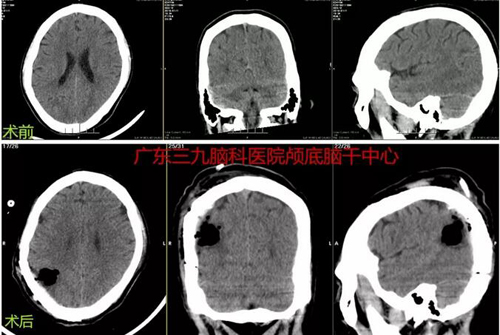

图2:术前CTA示右侧顶叶动静脉畸形(小型)。术后CTA报告示现:右侧顶叶动静脉畸形切除术后改变,术区及术区边缘未见明确异常血管影;右侧大脑中动脉下干远端分支仍稍增粗。

图3:术前术后CT对比示右侧顶叶动静脉畸形切除术后改变。